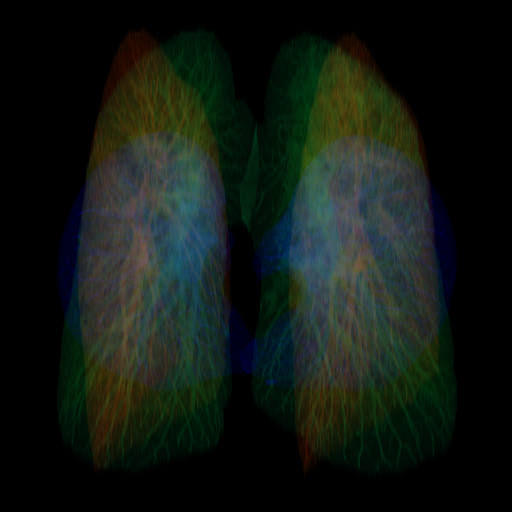

- 1.2 Examples of homogeneity in medical imaging modalities illustrating the similarity of the underlying subject (PET, CT, and MRI).

- (a) PET scan of the brain77footnotemark: 7

Thirdly, while seeming counter to the second point, while in a broad sense medical images are heterogeneous due to the very different imaging techniques and separation based on medical specializations (head scans vs foot scans), within a given data type, there is very high visual similarity. For example, all chest X-rays will look very similar due to standardized acquisition methods and tools, but also in large part, due to the high homogeneity of the human biology, see figure 1.2. For the chest scan example, most human bones and organs will have almost identical structures, similar sizes, and composition. Furthermore, the way these scans are collected is standardized, so the patients will all be positioned at the same angle and distance from the imaging machines. This is true even for data samples that have completely different labels, as the characteristics that indicate one diagnosis or another are often identified by very small, granular differences, which are visually very small in absolute terms. This poses a challenge to researchers in the sense that they can’t directly adapt many of the more recent and best-performing classes of Self-Supervised methods, such as contrastive learning. This has allowed us to develop methods that are tailored specifically for medical images.